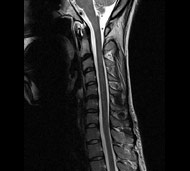

Спинальна магнітно-резонансна томографія (МРТ). Замість радіаційного випромінювання в МРТ використовуються потужні магнітні і радіохвилі для отримання зображення поперечного перерізу хребта. МРТ чітко відображає спинний мозок і нерви і забезпечує краще зображення пухлин кісток, ніж комп'ютерна томографія (КТ). Вам можуть ввести в вену кисті або передпліччя контрастну речовину, яка висвітлює деякі пухлини. Крім цього, використовують сканери з високою інтенсивністю сигналу для виявлення невеликих пухлин, які можна не помітити.